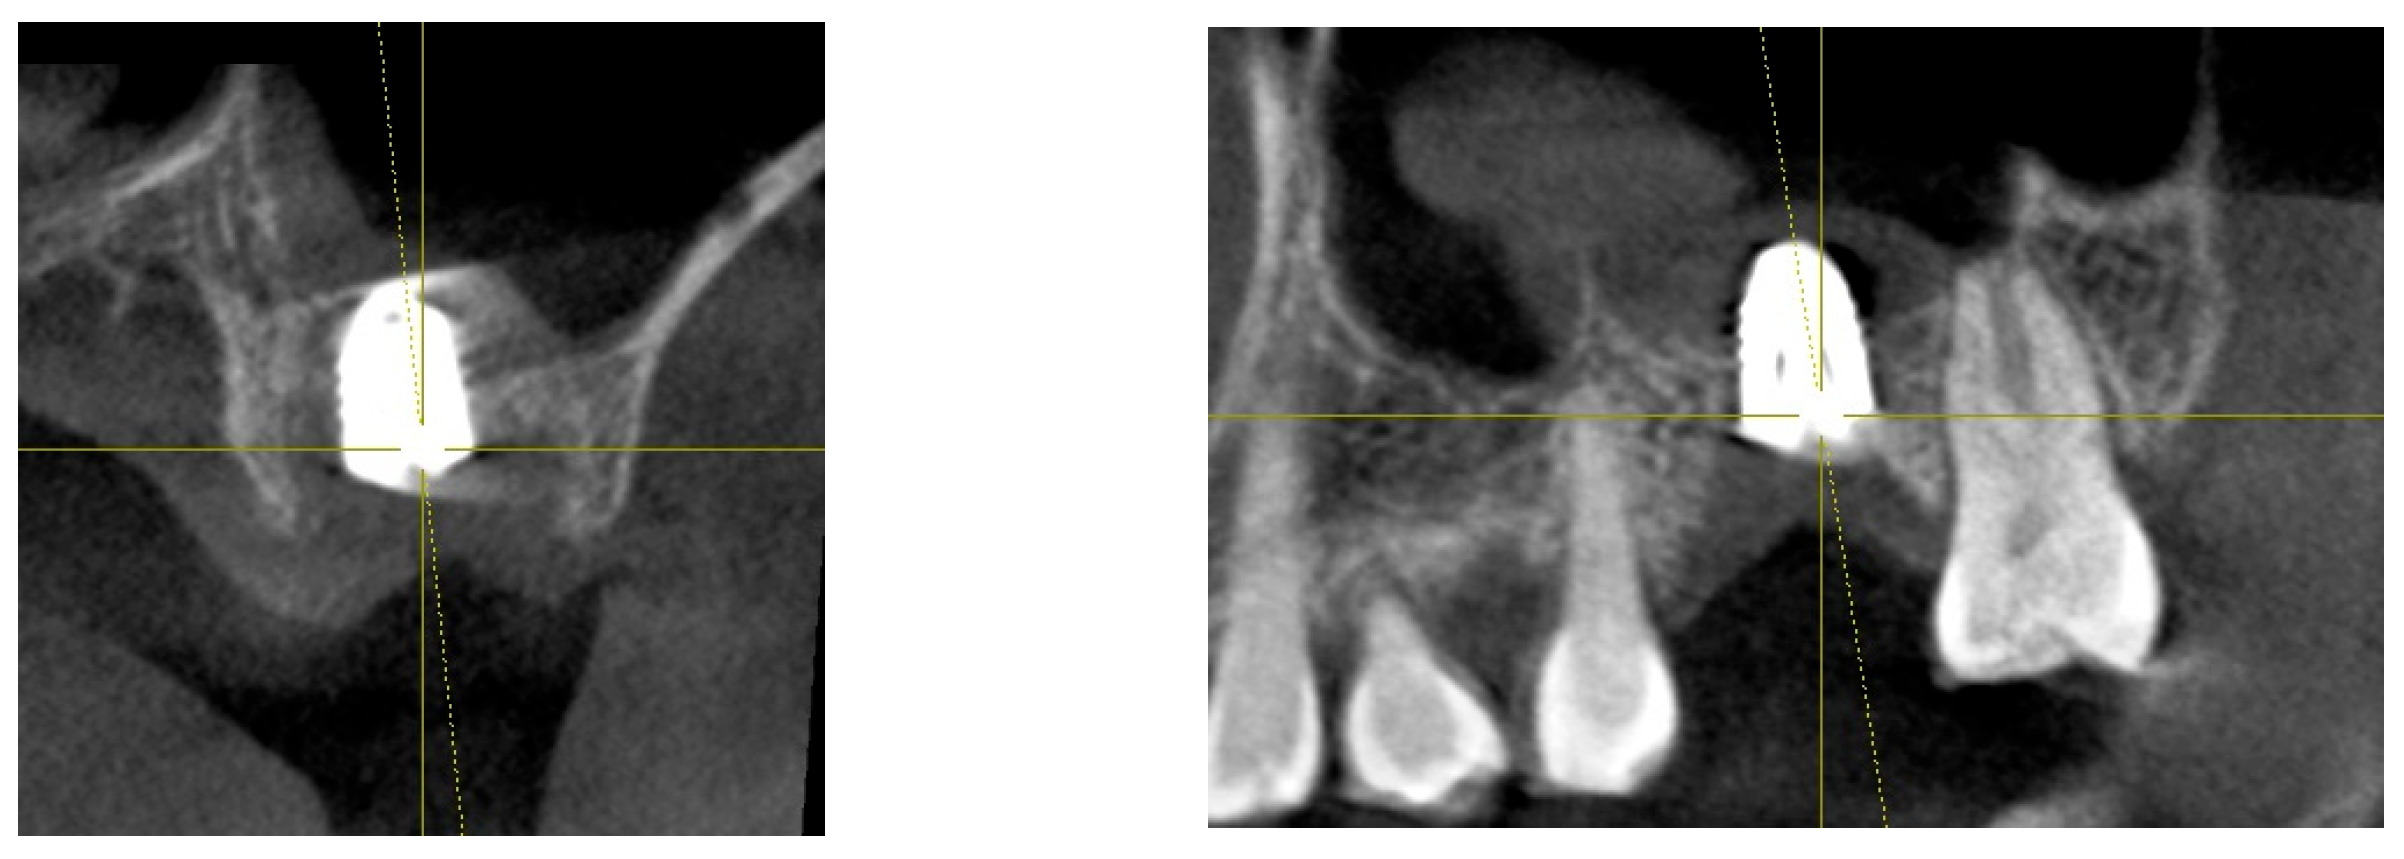

These two implant sites serve as a comparison for a split-mouth study. CBCT scans taken in 2021 and 2024 were utilized for a three-dimensional analysis of peri-implant soft tissue and bone structure.

Measurements of CRD changes for both implant sites (control and treatment) were conducted using Cone Beam Computed Tomography (CBCT). The analysis focused on parameters such as Crest to Restoration Distance (CRD), Depth of Placement (DP), and other structural features using CBCT imaging, complemented by clinical assessments. The primary objective was to evaluate how changes in CRD correlate with peri-implant health and disease, particularly in managing peri-implant mucositis.

Figure 7 and Figure 8 illustrate the radiographic changes observed from 2021 to 2024 at the lower right first molar implant site (control site) and the upper left first molar implant site (experimental site), respectively. (Figure 7, Figure 8) The clinical photographs taken in 2024 (Figure 9) depict the final results, showcasing both a stable and natural appearance for both implant sites.

Figure 7. This image illustrates the X-ray measurements conducted on the lower right first molar implant, comparing data from 2021 and 2024.

Preprints 151394 g007

Figure 8. This image illustrates the X-ray measurements conducted on the upper left first molar implant, comparing data from 2021 and 2024..

Preprints 151394 g008